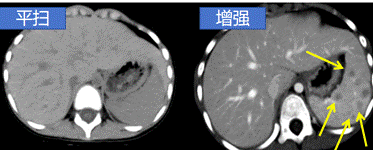

增强CT是在检查前先将含碘的对比剂注射进静脉后再进行扫描,是对平扫CT的补充,由于碘对比剂进入血液后,血液中含碘浓度升高,在病变部位与器官中的碘浓度形成密度差异,这样显影就更加清晰,更有利于对病灶范围、数量及性质等做出判断。因此,增强扫描是对CT平扫的补充,可以理解为CT平扫的升级版。

显示病变的边缘和内部结构:有些病变在平扫CT上可能难以清晰地显示其边界和内部构造。增强CT可以使病变的边缘更加清晰,有助于医生准确定位和评估病变的性质。

提高病变的检出率:在一些情况下,疾病早期病变较小,或者病变与周围正常组织的密度差异较小,平扫CT可能无法明确显示病变。通过增强CT,病灶或异常区域的对比度增加,病变更容易检测和诊断。